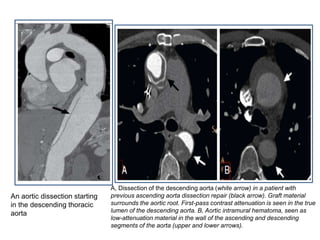

An aortic dissection starting

in the descending thoracic

aorta

A, Dissection of the descending aorta (white arrow) in a patient with

previous ascending aorta dissection repair (black arrow). Graft material

surrounds the aortic root. First-pass contrast attenuation is seen in the true

lumen of the descending aorta. B, Aortic intramural hematoma, seen as

low-attenuation material in the wall of the ascending and descending

segments of the aorta (upper and lower arrows).

An aortic dissectionstarting in the descending thoracic aorta A, Dissection of the descending aorta (white arrow) in a patient with previous ascending aorta dissection repair (black arrow). Graft material surrounds the aortic root. First-pass contrast attenuation is seen in the true lumen of the descending aorta. B, Aortic intramural hematoma, seen as low-attenuation material in the wall of the ascending and descending segments of the aorta (upper and lower arrows).